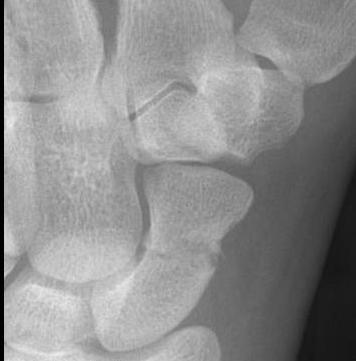

CT

Indication: any potential displacement

Position: patient prone with fully pronated hand over head

Scaphoid waist fracture 1 mm displaced

Scaphoid fracture with significant displacement

Scaphoid proximal pole fracture